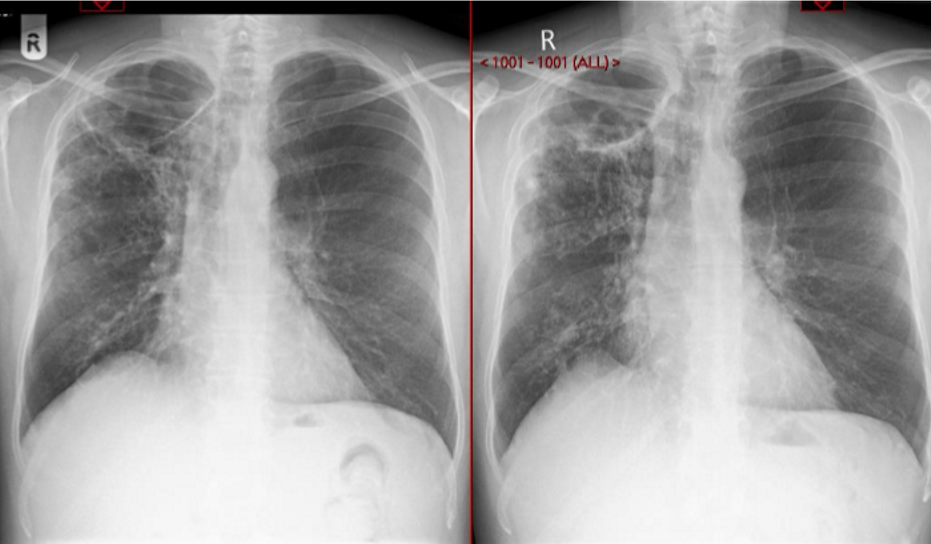

What is this ?

Cavitating NTM disease